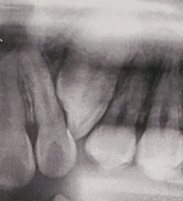

Hello, my orthodontist told me that I had to extract premolars because I don't have enough space and I have a trapped canine that hasn't come out. Should I remove the premolars? This is a doubt that has been on my mind.

(I will post my panoramic x-ray so you can help me)

(I will post my panoramic x-ray so you can help me)